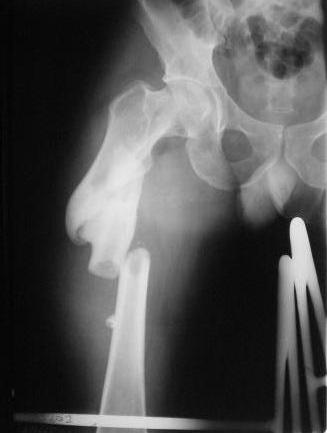

Пациент 33 лет поступил 1.02.08 с диагнозом: Множественная травма.

Т-образный перелом свода, перелом заднего края правой вертлужной

впадины. Поперечный подвертельный перелом диафиза, подвздошный вывих

правого бедра. Поперечный подвертельный перелом диафиза на фоне

консолидированного косого перелома в\3 левого бедра в порочном

положении. Открытый краевой перелом надколенника правого коленного

сустава. Открытый оскольчатый перелом н\челюсти. Закрытый неосложненный

перелом V ребра справа. В настоящее время больной компенсирован.